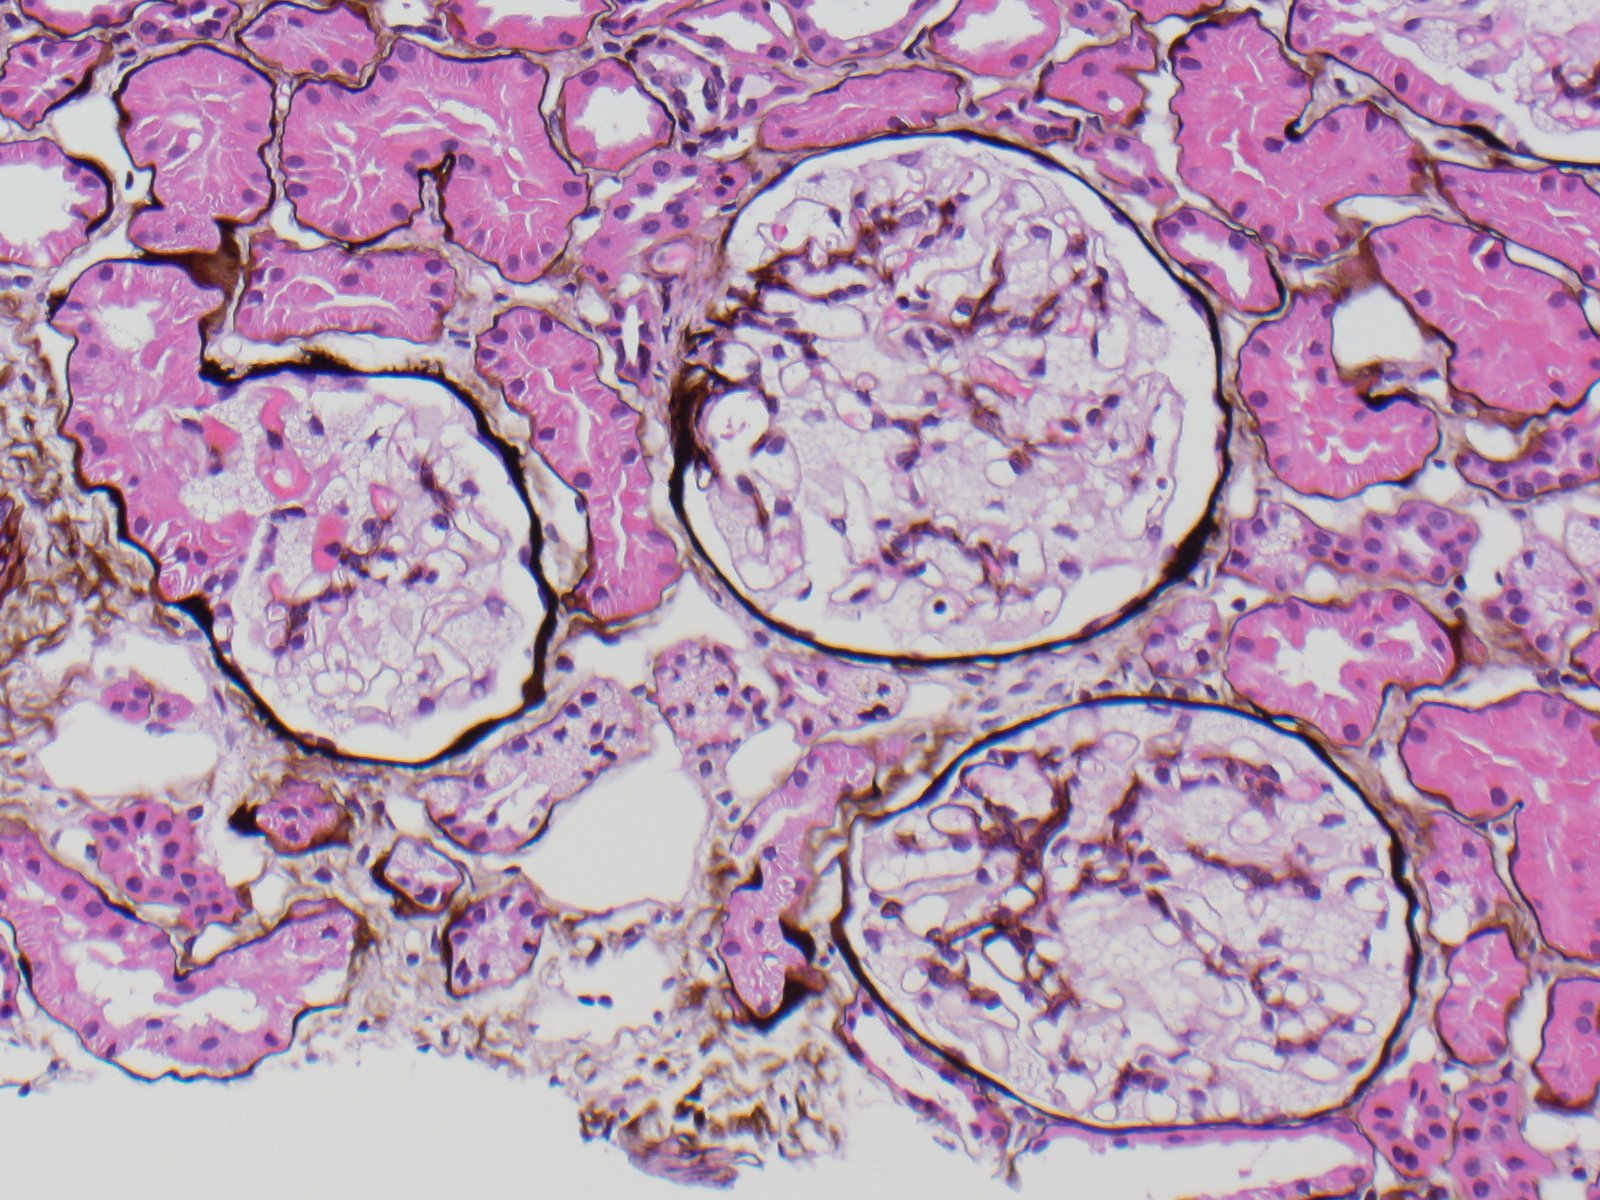

Fabry disease is an X-linked deficiency of alpha-galactosidase A leading to intracellular accumulation of glycosphingolipids. Clinical manifestations are systemic because this enzyme is present in lysosomes throughout the body; they include painful neuropathies, skin lesions (classically angiokeratomas), cardiovascular and renal disease (commonly proteinuria). By light microscopy, the accumulated galactosyl ceramide appears as vacuolization of podocytes and tubular cells because it is extracted by the xylene used in processing. By electron microscopy, lamellated inclusions called myelin or zebra bodies are most prominently present in podocytes, but are also variably present in endothelium, tubules and interstitial cells. Genetically engineered alpha-galactosidase A can now be used to treat patients, resulting in decreased disease manifestation.